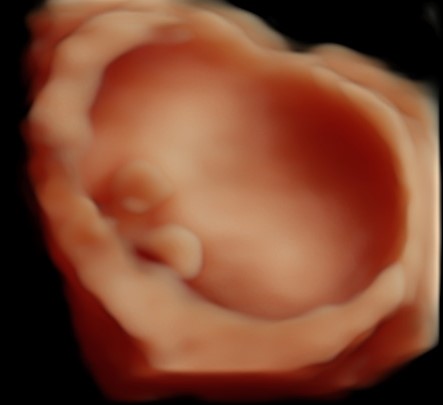

Monmouth County’s First 4D/5D/HD Live Ultrasound Studio

4D/5D/HD Ultrasound Gallery

Gallery